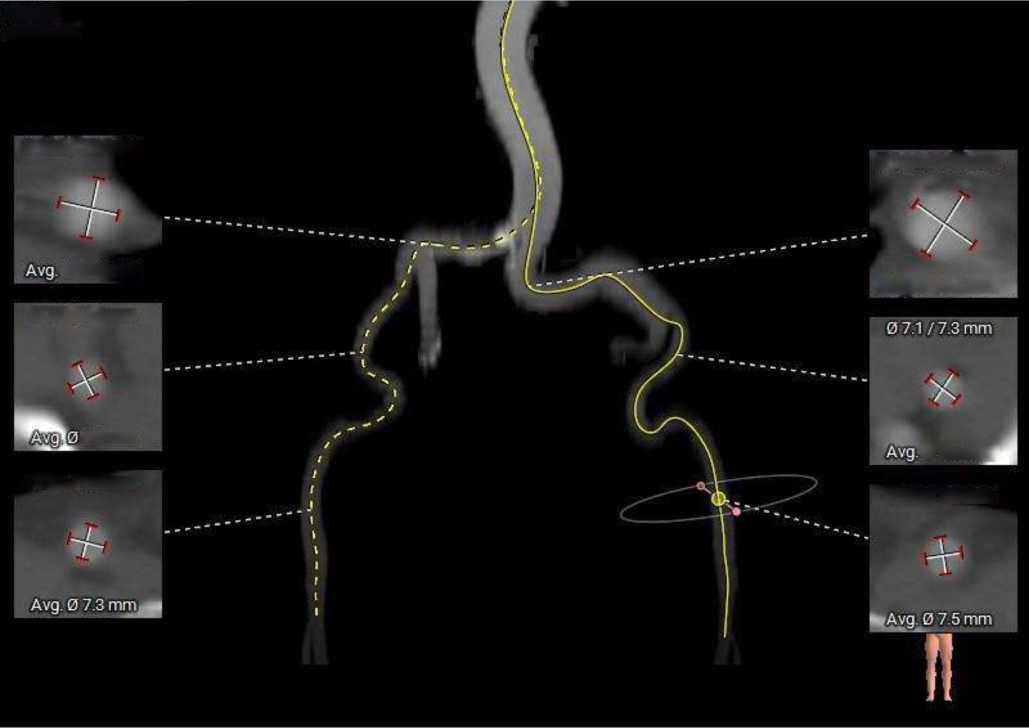

外周入路走行迂曲,左侧髂总存在67度锐利夹角,胸主和右侧髂总存在少量散在钙化,血管内径可,血管内壁存在钙化和不规则纤维增厚。

外周血管及主动脉弓解剖:

术前考虑右侧股动脉为主入路,左侧为辅助入路。三叶式主动脉瓣,中度钙化,钙化主要分布于瓣叶附着缘及对合缘,钙化分布不均,瓣膜锚定难度适中,瓣膜植入受瓣叶及钙化挤压存在少量瓣周漏风险。双侧冠脉幵口高度可,左冠切线角度测量瓣叶大于LCA开口下缘到根部距离,结合瓦氏 窦及STJ尺寸预估,冠脉风险适中,建议术中密切灌注左冠灌注情况。水平夹角68度,横位心,主动脉弓宽度、角度尚可,弓部存在散在钙化;左室腔内径偏 大、心室壁稍增厚,心尖部较薄,室壁瘤膨出不排除,建议超硬导丝塑形大一点,注意 不要过度用力顶到心尖部位。外周入路走行迁曲,左侧髂总存在67度锐利夹角,胸主和右侧髂总存在少量散在钙化, 血管内径可,血管内壁存在钙化和不规则纤维增厚,入路穿刺规范操作,小心通过,避免入路血管损伤及相关并发症。为避免手术并发症,手术预装AV29瓣膜,根据23mm球囊预扩结果选择瓣膜型号,计划瓣环下零位幵始释放。